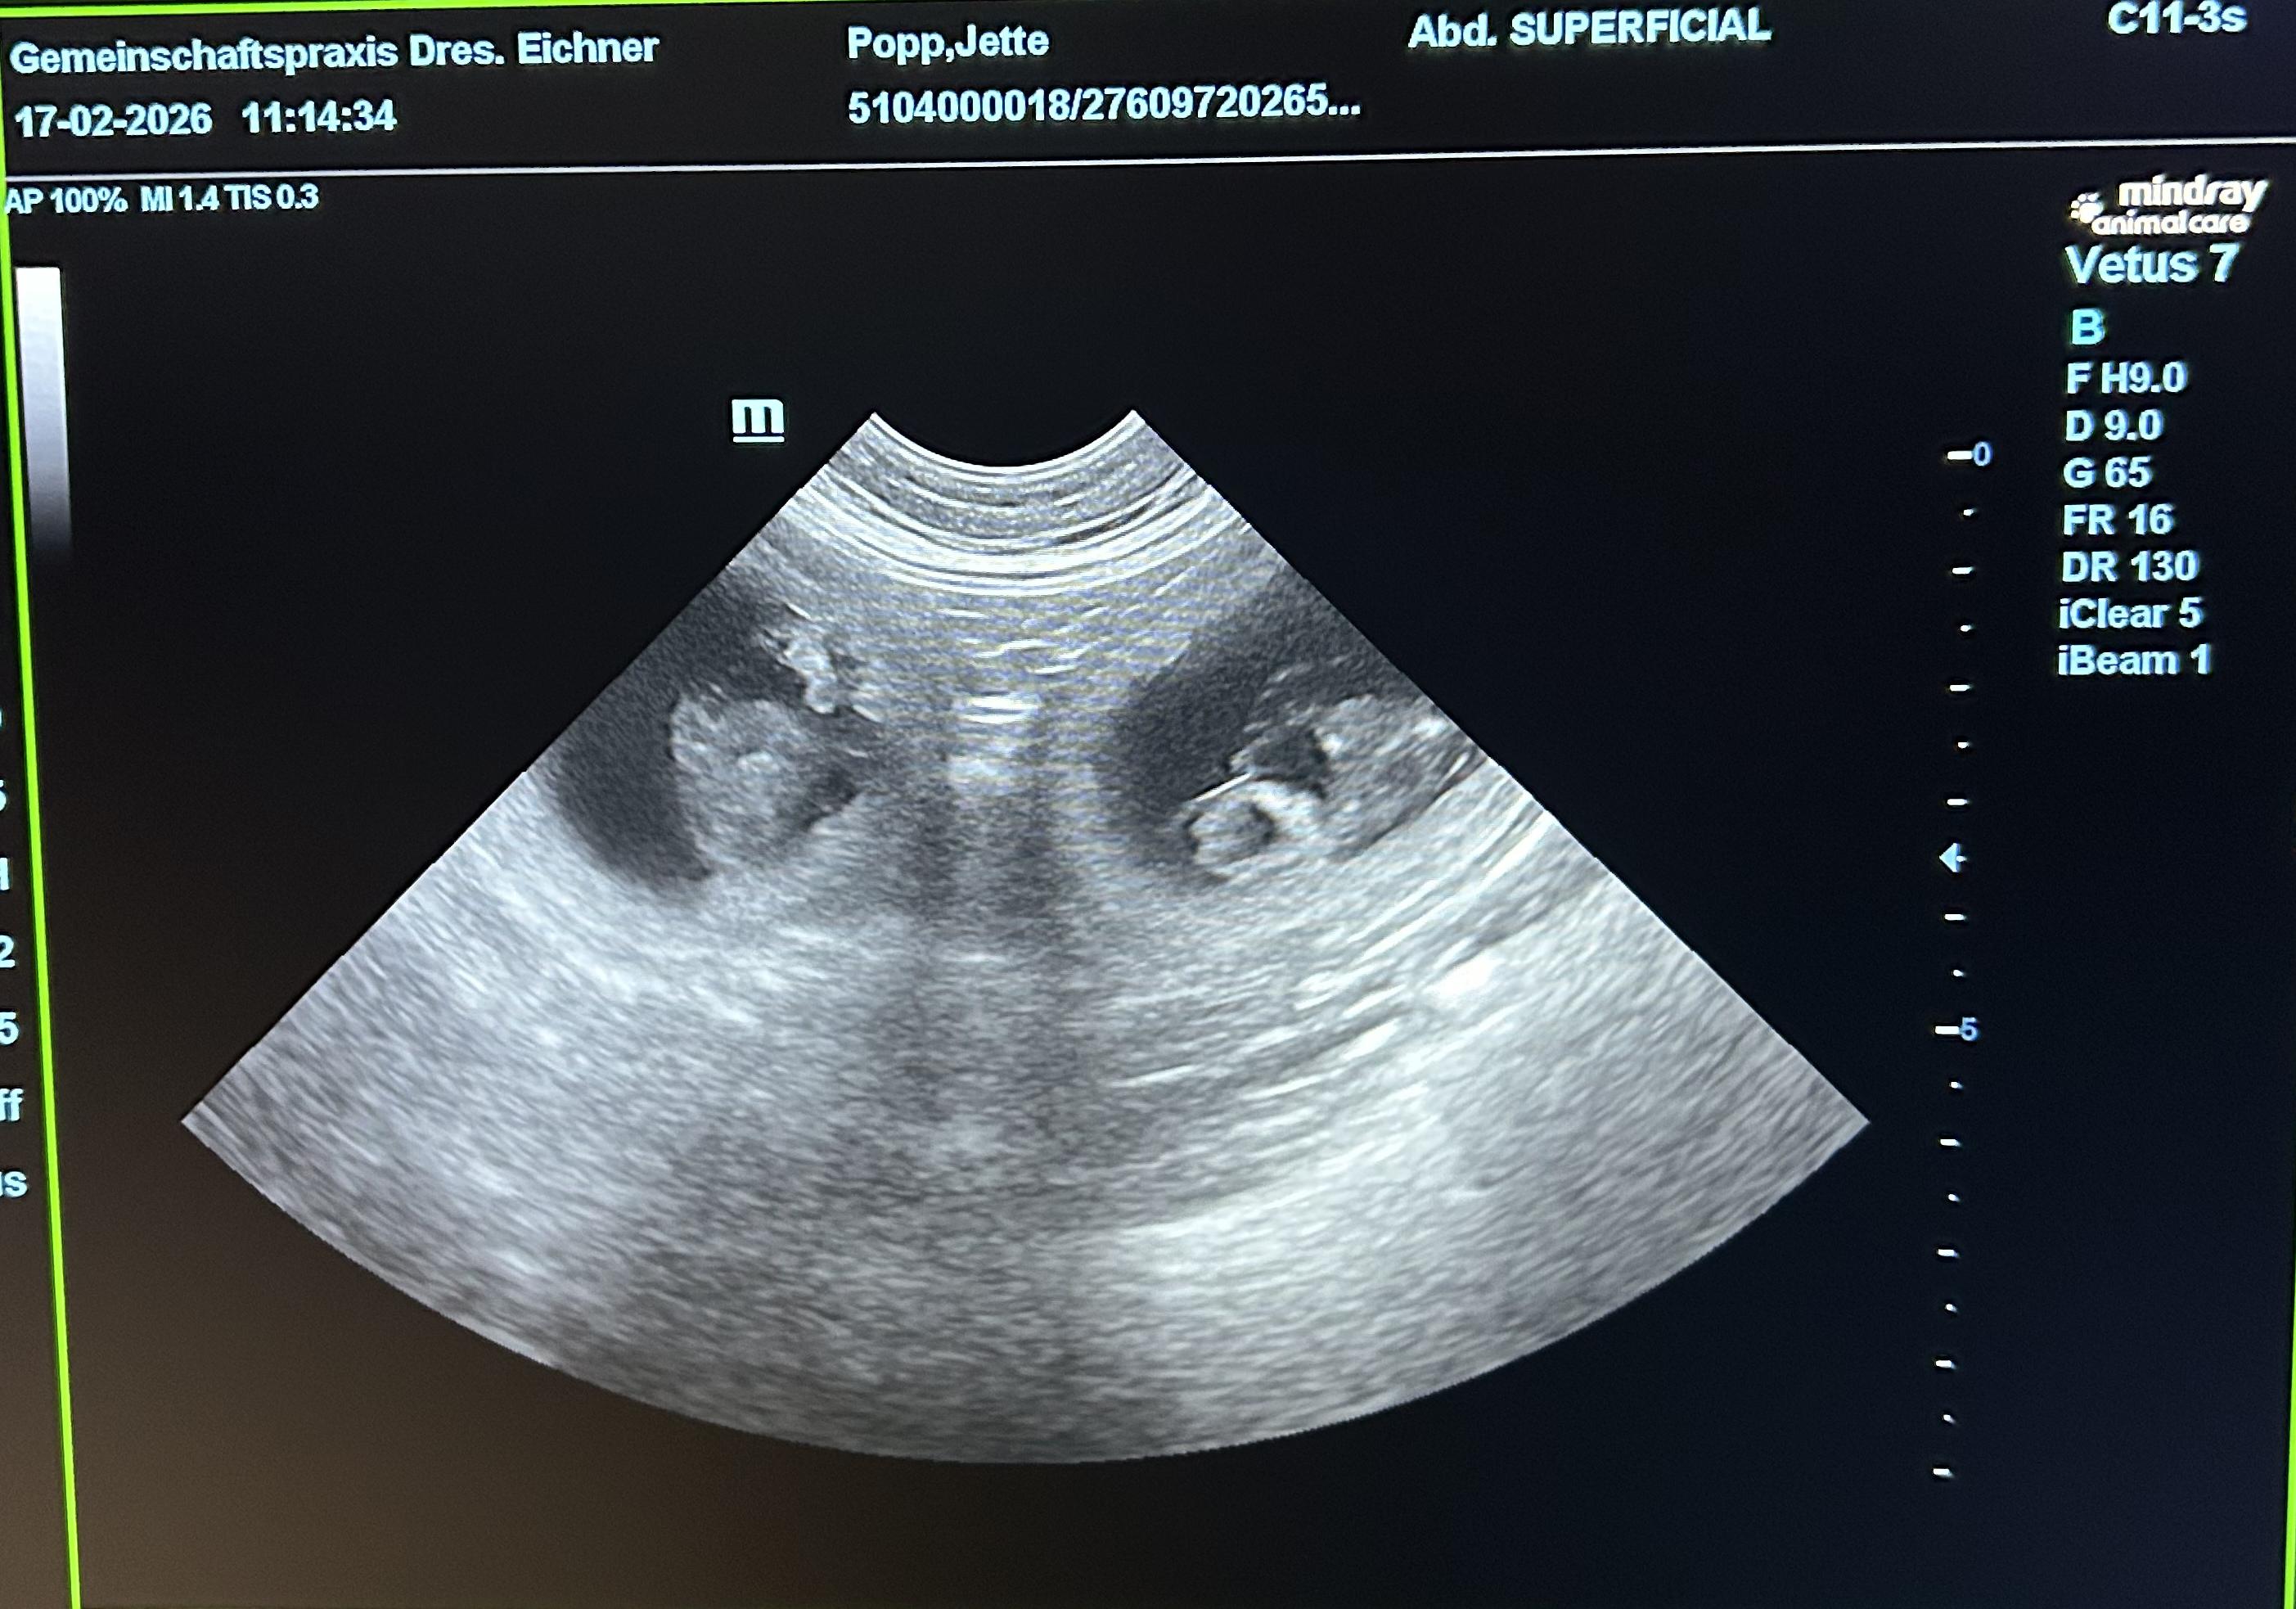

Jettes Welpen 2026

Dt.J. Ch. VHD & Club Scottsdale Xircus as Nonchalance "Jette" |